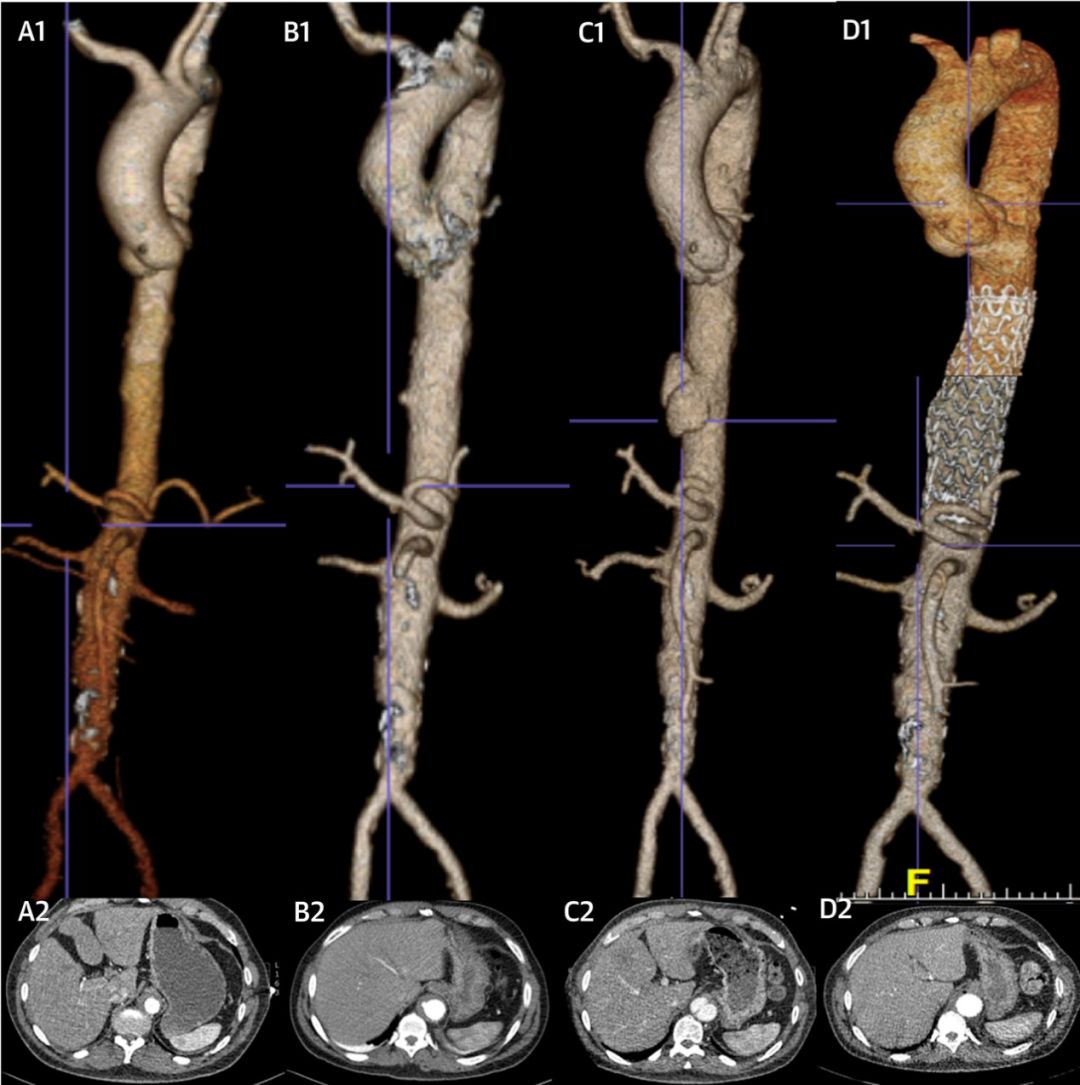

为患者进行了心电图、经胸超声心动与冠脉造影检查,初步排除了ACS的可能性。随后为患者进行了主动脉CTA检查,显示主动脉弓远端与降主动脉存在壁内血肿,好在还未出现连通、溃疡与夹层(图A1/A2)。

图1 入院(A)、7天(B)、30天(C)、术后(D)的主动脉CTA

入院后将血压控制于SBP 100-110mmHg左右,但患者在第7天时复查主动脉CTA仍发现降主动脉的壁内血肿进展为穿透性主动脉溃疡,并且怀疑已经出现主动脉夹层(图B1/B2)。在30天时再复查主动脉CTA,降主动脉处的穿透性溃疡进展为Stanford B型主动脉夹层与假性动脉瘤,但主动脉弓远端的壁内血肿自行吸收(图C1/C2)。在整个进展过程中患者一直没有症状。

考虑到保守治疗下降主动脉病变不断进展,于是在全麻下使用TEE与X线透视指导对患者进行了胸主动脉腔内修复术(thoracic endovascular aortic repair, TEVAR)。3个月后复查主动脉CTA显示主动脉夹层假腔内已经形成血栓,主动脉形态稳定(图D1/D2)。